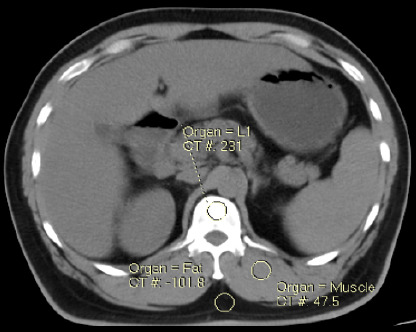

Methods: This is a prospective study and included a total of 141 patients (females: 71, males: 70) referred for contrast enhanced computed tomography (CECT) abdomen. First, the plain scan of abdomen was done. Contrast media was injected intravenously followed by acquisition of arterial and portovenous phase (PV) of abdomen. Plain, arterial and PV phases axial CT images were loaded on Philips BMD analysis application. A circular region of interest (ROI) measuring 30-40 mm2 was placed at all five lumbar vertebrae (L1-L5) and value of BMD was obtained in mg/cm3.

Results: Paired t-test was used to compare BMD in plain, arterial and PV phase. There was significant difference (p <0.05) in BMD (L1-L5) between plain (110.86±36.61 mg/cm3), arterial (117.04±37.95 mg/cm3) and PV phase (127.52±40.9 mg/cm3). The study also noted significant difference between males and females in BMD of lumbar spine (L1-L5) for plain and CECT abdomen (p <0.05).